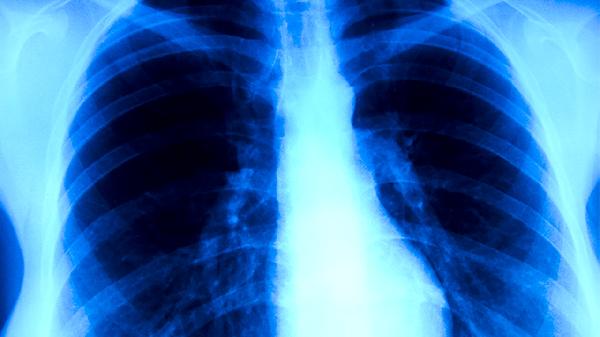

肺结核药物治疗

肺结核药物治疗通常需要遵医嘱使用异烟肼片、利福平胶囊、吡嗪酰胺片、乙胺丁醇片、链霉素注射液等抗结核药物。肺结核是由结核分枝杆菌感染引起的慢性传染病,药物治疗需遵循早期、联合、适量、规律、全程的原则。

肺结核患者除规范用药外,需保证充足营养摄入,多吃高蛋白食物如鸡蛋、瘦肉、豆制品等。适当进行散步、太极拳等温和运动有助于增强体质。治疗期间应严格戒烟戒酒,保持居住环境通风良好。定期复查胸部影像学和痰菌检查,全程完成6-9个月的治疗周期。出现药物不良反应应及时就医调整方案,不可自行停药或更改剂量。密切接触者应进行结核菌素试验筛查。